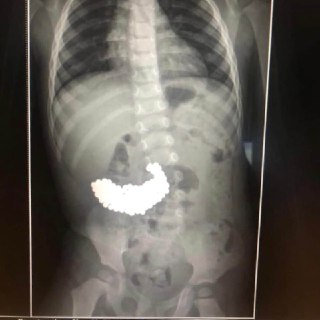

Лікарі витягли 209 магнітних кульок зі шлунка дворічної дитини.

Кульки від магнітного конструктора видалили ендоскопічно — без розрізів та проведення відкритої операції. Під дією шлункового соку деякі з них стали гострими. Крім того, кульки притягувалися до металевого захоплювача, що значно ускладнювало процес. Операція тривала дві години.